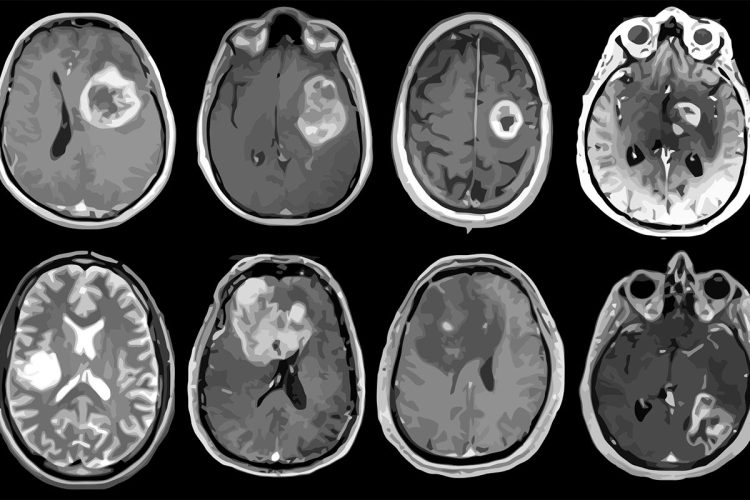

The study, in JAMA Network Open, looked at cancer records from 1992 to 2018 for 3.8 million people in the U.S. They checked cases of cancer that spread to other parts of the body. They compared Generation X to older groups like Baby Boomers and the Silent Generation. The study found that some cancers, like colon, rectal, thyroid, ovarian, and prostate cancers, are getting more common even though medicine is getting better.

Rosenberg and Adalberto Miranda-Filho think more people in Generation X will get certain cancers. Thyroid, kidney, rectum, and colon cancers will go up. Women will have more pancreatic, ovarian, and endometrial cancers. Men will get more prostate cancers and leukemia. Lung cancer will go down for everyone. Men will see fewer liver and gallbladder cancers. Women will have less cervical cancer.